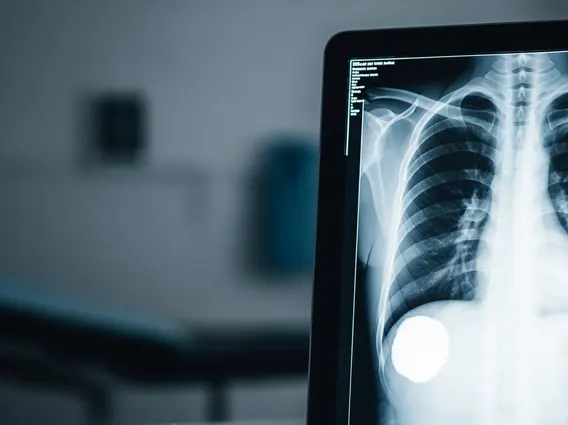

Diagnosing pleural effusion involves a combination of physical examination, imaging studies, and fluid analysis. During a physical exam, a doctor may detect dullness to percussion and decreased breath sounds over the affected area. Imaging tests are essential for confirming the presence of fluid and assessing its extent:

- Chest X-ray: Often the first diagnostic tool, showing fluid as a white area at the base of the lung.